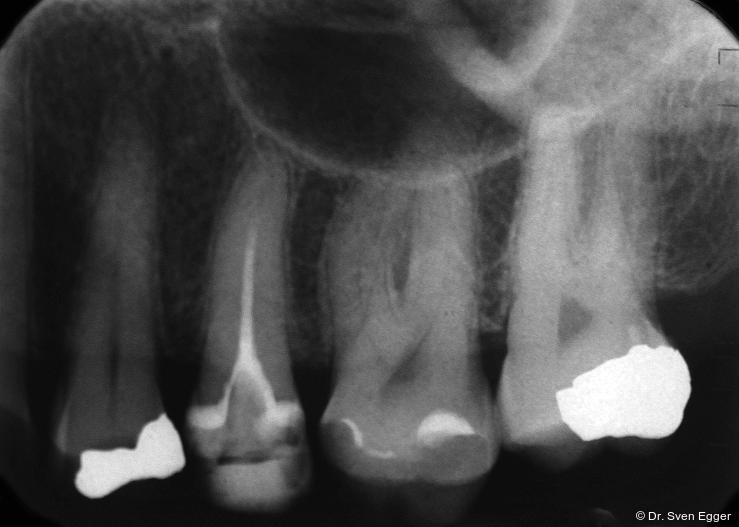

Das OPG zeigt insuffiziente endodontische Versorgungen an 15, 25 und 46. Die Kieferhöhle rechts zeigt eine kirschgroße, kugelige Verschattung (Überweisung/Abklärung Kieferchirurgie).

Die Follow-up-Untersuchung zeigte ein Ergebnis, mit dem die Patientin nach 15 Jahren Tragezeit weiterhin vollumfänglich zufrieden ist. Die keramische Teilkrone an Zahn 17 wurde am 31.5.2022 aufgrund Debondings nach erneuter Konditionierung wieder eingesetzt. Die Kieferhöhlen sind verschattungsfrei und zeigen keine Anzeichen eines Rezidivs der in 2007 erfolgten Zystenoperation in der rechten Kieferhöhle (Mukozele). Die endodontisch revidierten Zähne 25 und 45 zeigen weder klinisch noch röntgenologisch Auffälligkeiten. Die Stellung der Ober- und Unterkieferfront sowie die in ZKP etablierte horizontale und vertikale Relation des Unterkiefers ist stabil und bereitet keinerlei Schwierigkeiten. Die Implantate weisen klinisch und röntgenologisch schöne Hart- und Weichgewebsverhältnisse auf. Die häusliche Mundhygiene ist sehr gut. Es sind keine Anzeichen einer Funktionsproblematik zu erkennen. Die Michigan-Schiene wurde 2022 erneuert. Für die vorliegende Situation lässt sich damit auch weiterhin eine sehr gute Langzeitprognose aussprechen (Abb. 18–25).